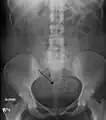

Multiple uterine leiomyoma with calcification

Fibroids are monoclonal tumors and approximately 40–50% show karyotypically detectable chromosomal abnormalities. When multiple fibroids are present they frequently have unrelated genetic defects. Specific mutations of the MED12 protein have been noted in 70 percent of fibroids.[29]